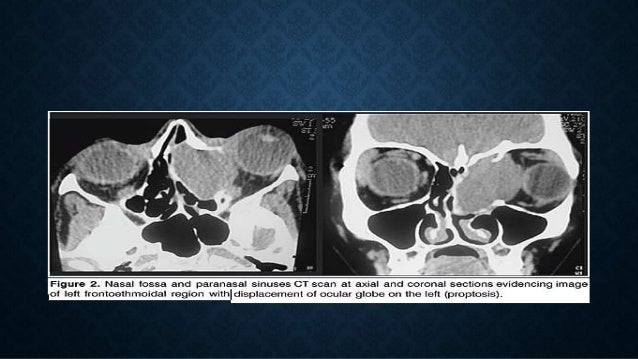

8. 8. • En el desarrollo ilimitado, destruye los tabiques óseos e invade los senos paranasales, llegando a deformar la fascies: la pirámide nasal se ensancha, se aplasta y por lo general se desvía, la invasión de la orbita produce exoftalmia, la cara se ensancha y el paciente respira con la boca abierta: CARADE SAPO.

10. 10. Clínica de inicio: tumor duro, muy sangrante en varones y adolescentes. Imagenología: Rx 3 incidencias frente, perfil y base de cráneo, TAC Y RMN. L a biopsia ESTA CONTRAINDICADA